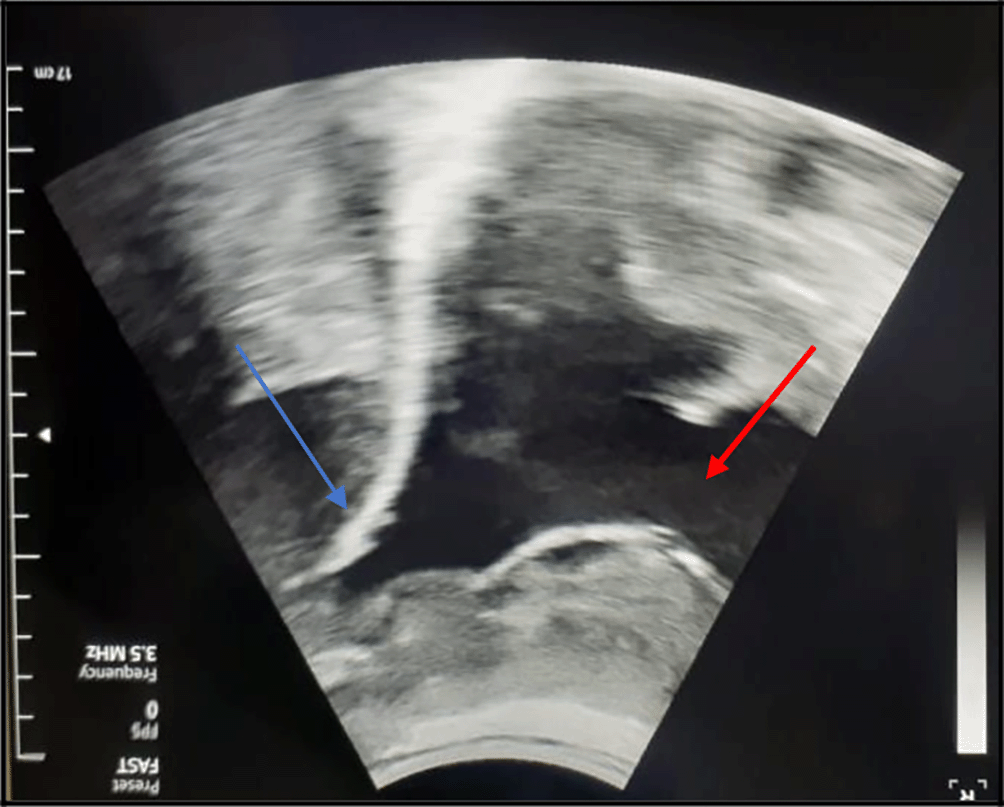

The chest X-ray showed left pleural opacity with signs of compression (Figure 1). So, an exploratory and evacuating ultrasound-guided pleural puncture was immediately performed. The thoracic ultrasound showed a massive anechoic, free left pleural effusion associated with pleural nodules (Figure 2). Analysis of the pleural fluid showed a serohaematic exudative fluid with a predominantly lymphocyte formula (80%). A Gram stain fast bacilli (AFB) stain and bacterial and tuberculosis cultures for were all negative. Therefore, a malignant origin was suspected. The chest CT-scan revealed a left-sided malignant pleural effusion associated with mediastinal adenopathy, extended secondary bone lesions and subcutaneous lesions (Figure 3). Additionally, the echocardiography was normal.